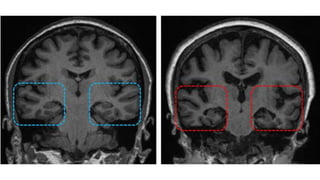

The document discusses various types of dementia, including Alzheimer's dementia characterized by medial temporal lobe atrophy, frontotemporal dementia involving degeneration of the frontal and temporal lobes, vascular dementia due to multiple infarcts, and Creutzfeldt-Jakob disease. It highlights the specific brain regions associated with Alzheimer's and frontotemporal dementia. The document is authored by Dr. Madhu Hasa Ghantasala, a 1st year resident in general medicine.